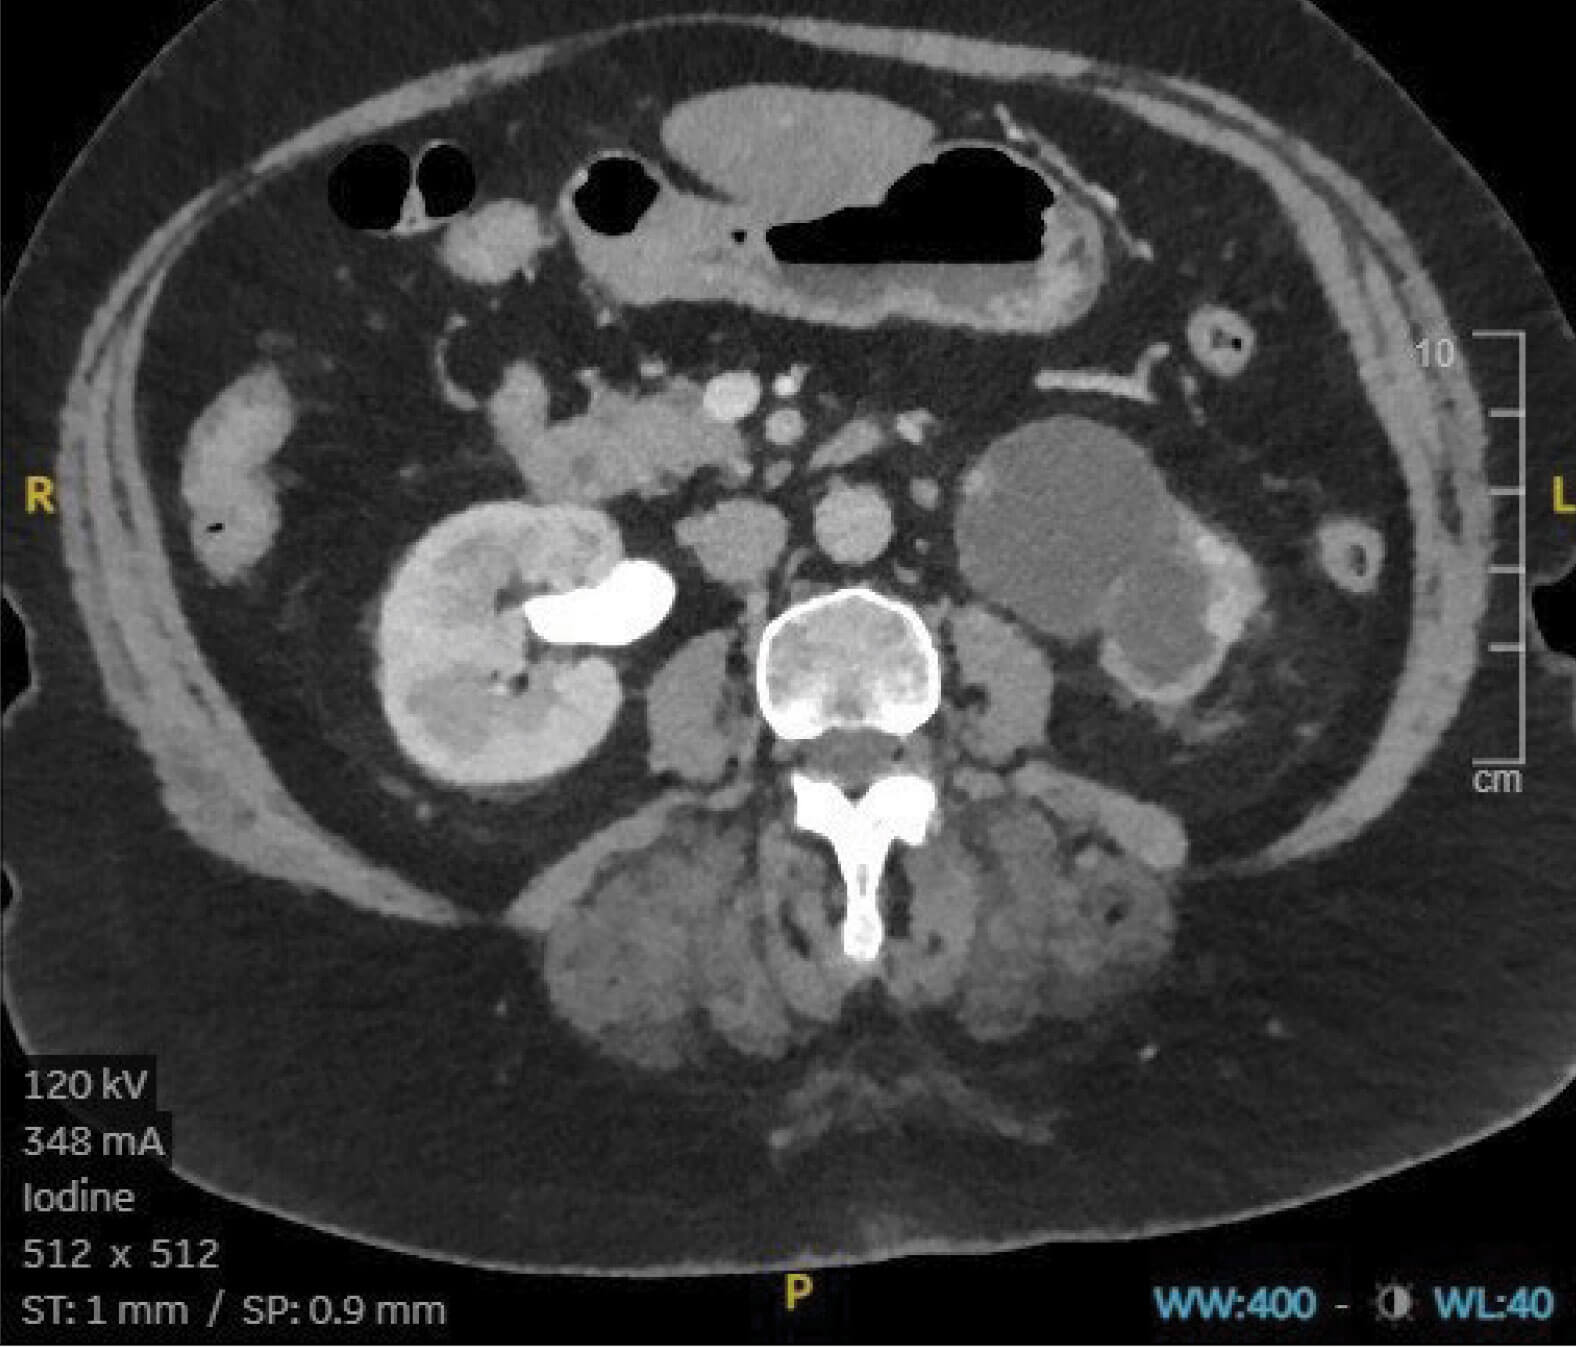

Figure 3.

- A 74-year-old female is noted on annual review to have a deterioration in her renal function. Following an ultrasound scan, a CT intravenous urogram (IVU) is performed, showing no hydroureter on either side, but what does Figure 3 show?

- A hydronephrotic left kidney with minimal renal cortex and no excretion of contrast into the collection system. Right kidney appears normal.